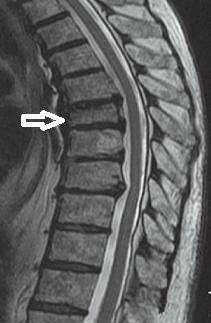

压缩性骨折就好比一个馒头被压扁了,但是又没有整个四分五裂,还是大致原来的环形轮廓。如果四分五裂了,那就是压缩性粉碎性骨折。

压缩性骨折经常出现于老年人,因为老年人的骨质疏松而导致骨质的强度明显减小,当受到垂直方向的暴力,会导致骨质的压缩变扁,从而出现压缩性骨折。

出现此类的情况多见于严重骨质疏松的老人在弯腰或者抬重东西的时候出现腰椎和胸椎的压缩性骨折。会即刻出现胸闷腰痛直不起腰,或者隐隐作痛,如果压缩性骨折并不是很严重的话,也很容易被遗漏。尤其是农村的留守老人,子女在外地工作的,来医院并不方便,所以多选择在家里面忍一忍。可随着时间的延长,疼痛并没有好转,再来医院检查的时候,骨折已经变成陈旧性的了。

有极少部分的骨折,并不会有明显的疼痛,或者只痛几天就好转了。但并不代表骨折恢复了。椎体的骨折一般要求:压缩小于1/2的可以保守治疗,卧床休息2到3个月,在医生的指导下逐渐的恢复坐立和行走。大于1/2的压缩性骨折是需要做手术的,目前常采用的治疗方案是pvp、pkp,是一种非常经济实用,效果好的治疗方案,比过去做钢板螺钉,撑开植骨要简单的多,但是任何手术方式都有它的缺点,具体情况也要具体分析。